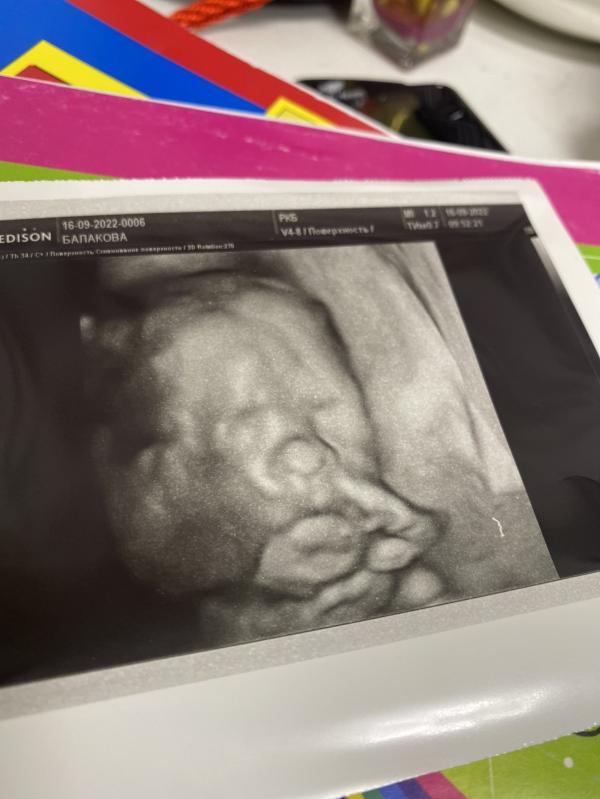

Даже 3D фоточку малышки сделали 😍🥰❤️

Это был как приятный бонус в конце обследования☺️